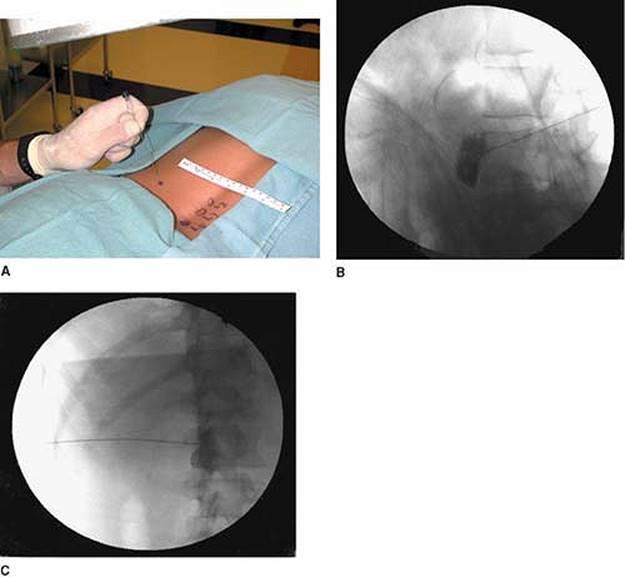

Approach and Technique: The lumbar region is prepared and draped using sterile techniques. The block is performed at the L3 level. The fluoroscopy beam is rotated 25° to 30° lateral to the midline toward the side to be blocked, and a fluoroscopic view is obtained. The upper lateral edge of the L3 vertebra is then isolated by keeping a sterile clamp tip at that point on the skin, and local anesthesia is applied to the skin and underlying tissues (Fig. 63-6A). The bent 22-gauge spinal needle is then introduced under the skin with the tip pointing laterally. The needle is advanced gradually toward the upper lateral border of L3 with the bevel pointing laterally. The lateral (Fig. 63-6B) and anteroposterior (Fig. 63-6C) views are taken to confirm the depth of the needle and its distance from the midline. The needle is advanced until it approaches the anterolateral margin of the vertebral body in the lateral view, taking care that the needle does not cross the facet line in the anteroposterior view. The bevel is then directed medially to hug the vertebral body anterolaterally. After negative aspiration for blood and cerebrospinal fluid, 5 mL of Isovue-200 is injected. After confirming spread of the dye in anteroposterior and lateral views, 5 mL of 0.5% bupivacaine is injected. Temperature recordings are obtained 5 to 10 minutes after the block and compared with the temperatures before.

Figure 63-6. Lumbar sympathetic block.